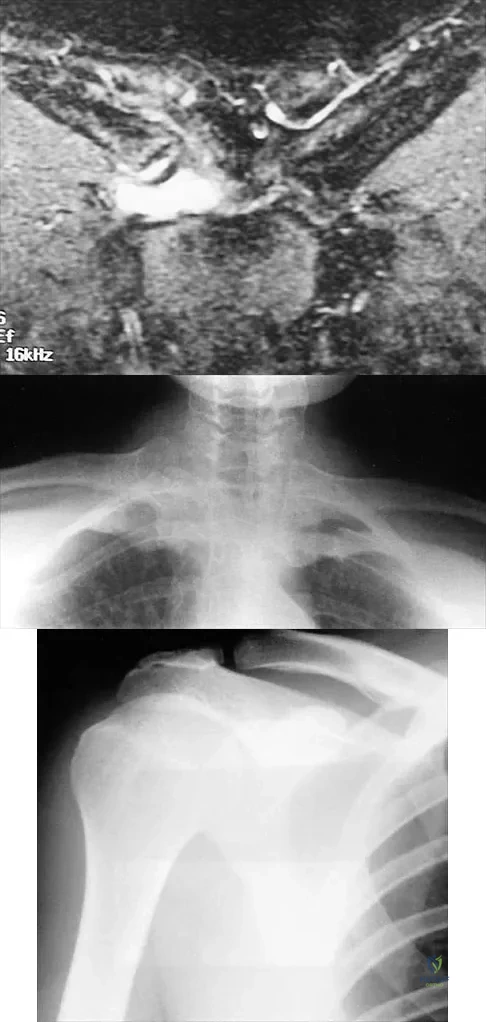

A 43-year-old former professional hockey player reports severe pain in his chest after being checked from the side in a pick-up hockey game. An MRI scan and plain radiographs are shown in Figures 25a through 25c. What is the most likely diagnosis?

Explanation

Question 69

A 55-year-old woman with a 15-year history of systemic lupus erythematosus has had left shoulder pain for the past 3 months. She reports that the pain has grown progressively worse over the past few months, and her shoulder function is severely limited. She is presently being treated with azathioprine and has used corticosteroids in the past. AP and axillary radiographs are shown in Figures 19a and 19b, and MRI scans are shown in Figures 19c and 19d. Which of the following forms of management will yield the most predictable pain relief and return of shoulder function?